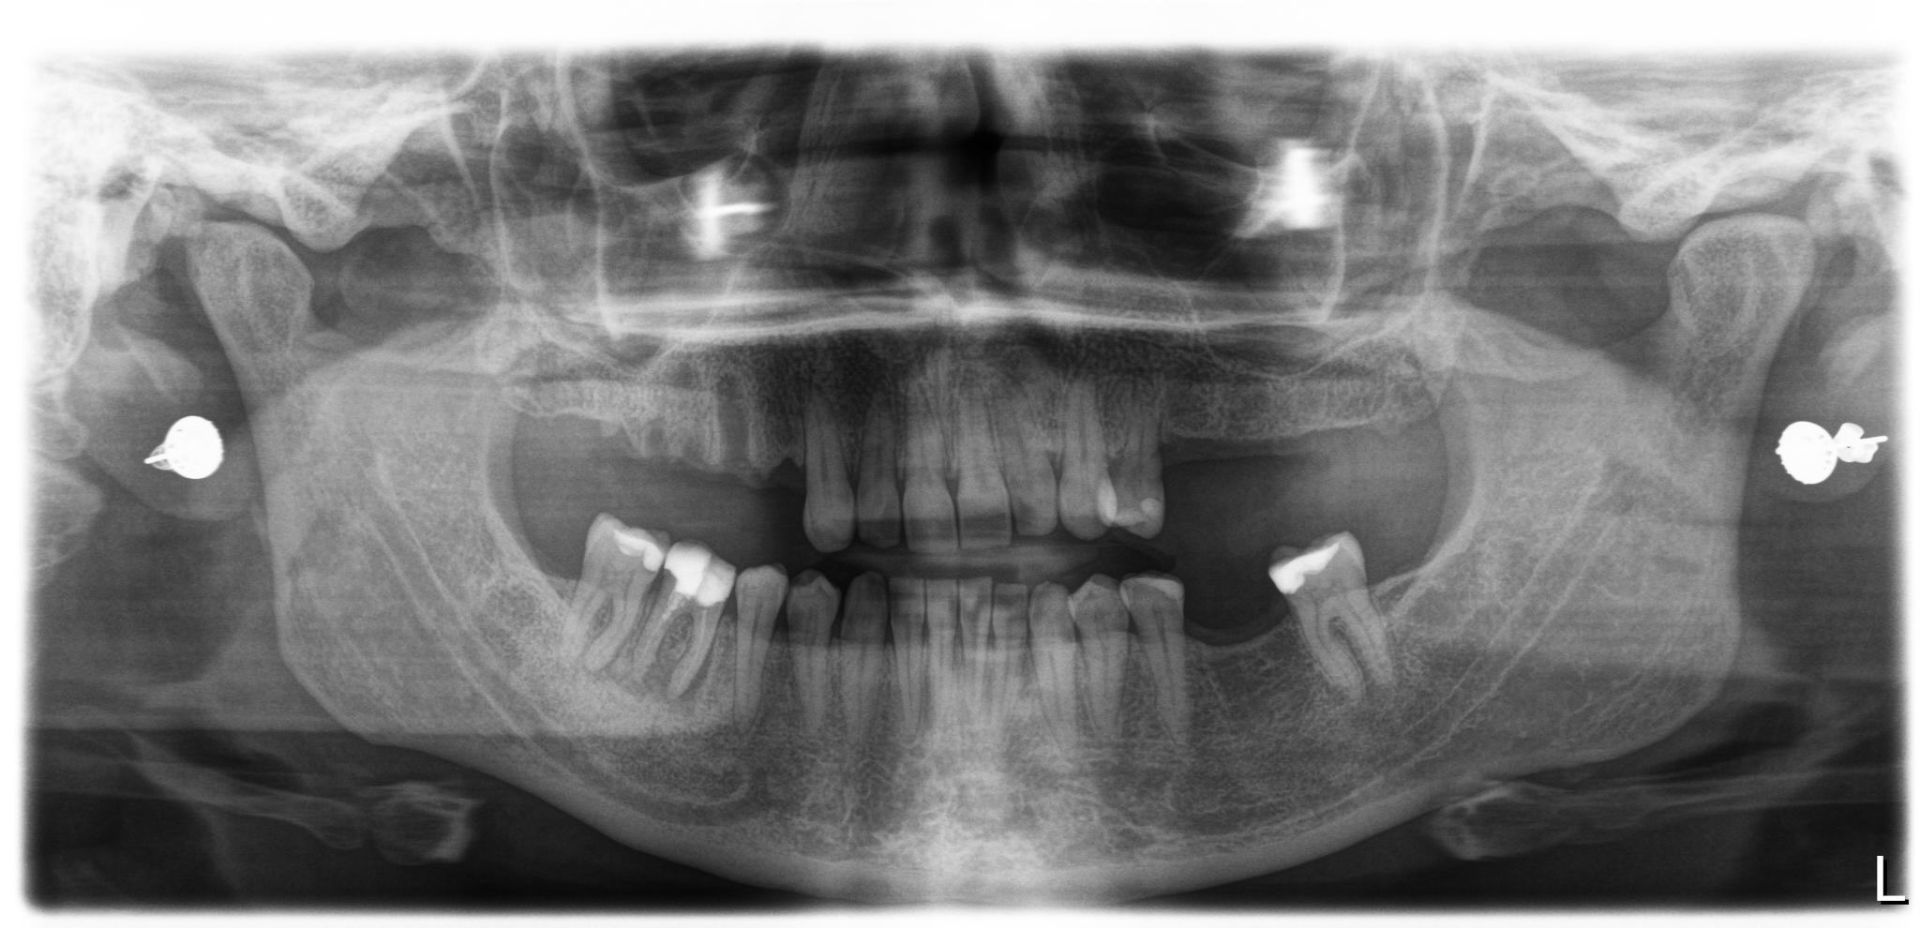

After

Zirconia bridge on Southern DC Implants